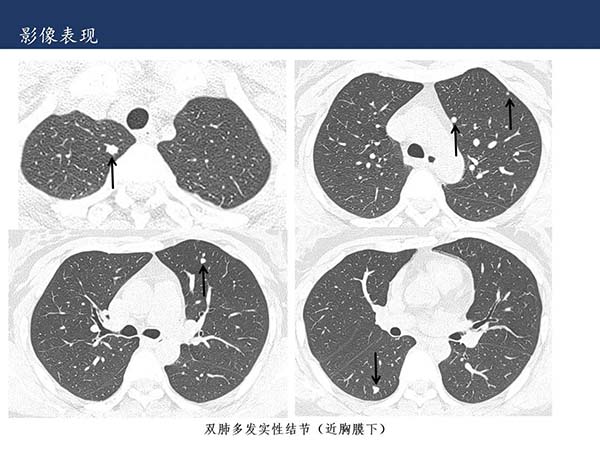

【杨柳科普】肺上皮样血管内皮瘤的影像表现